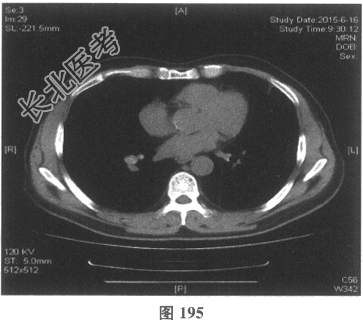

- 多项选择题4.[提示]患者应用多种抗生素治疗(第三代头孢菌素、青霉素加酶抑制剂)包括抗曲霉菌治疗无效,加用甲泼尼龙40mg静脉滴注病情好转。肺部CT检查显示病变明显改善。尿常规检查正常, 肾功能检测正常。复查肺部CT(图188~图195):示病变较前好转。Wegener肉芽肿的主要临床表现是( )